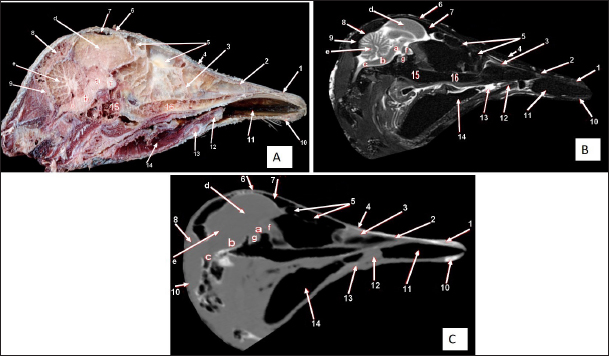

Fig. 2. Sagittal cross section of the adult ostrich head—level 1. A) Photograph of median sagittal anatomical section. B) MRI and C) computed tomography images showing: 1- Os premaxillare, 2- Culmen, 3- Nasal septum, 4- Os nasale, 5- Frontal sinus, 6- Frontal bone, 7- Cranial cavity, 8- Os parietale, 9- Os supraccipitale, 10- Os dentale, 11- Oral cavity, 12- Tongue, 13- Basihyoid, 14- Larynx, 15- Os basisphenoidale, 16- Vomer, and a- Optic lobe, b- Pons, c- Medulla oblongata, d- Cerebral hemisphere, e- Cerebellum, f- Optic chiasma and g- Pituitary gland.

The brain was divided into three parts: the hindbrain (medulla oblongata and cerebellum), the midbrain (cerebrum’s peduncles and optic lobes), and the forebrain (thalamus, pineal body, hypophysis, optic tracts, and chiasm, cerebral hemispheres, and olfactory lobes) (Figs. 2, 9, and 10). The sagittal section of the brain includes the olfactory bulb, cerebrum, cerebellum, medulla oblongata, optic lobe, optic chiasm, and hypophysis (Fig. 2). The dorsal median longitudinal fissure separates the cerebrum into two hemispheres. The sagittal prominence (west) was present on both sides of this fissure (Figs. 9 and 10).

The CT pictures revealed the skull as a readily discernible white structure due to its high CT density, while the brain appeared as a grey structure due to its intermediate density. However, the settings utilized made it impossible to identify different areas of the brain in the CT scans (Figs. 9 and 10C, F). The MRI pictures showed the brain as a whitish structure with a high signal intensity. This technique was used to identify various brain structures, including the hindbrain (medulla oblongata, and cerebellum), the midbrain (peduncles of the cerebrum, optic lobes), and the forebrain (thalamus, pineal body, hypophysis, optic tracts and chiasm, cerebral hemispheres, and olfactory lobes) (Figs. 2B, 9 E, and 10E). Additionally, the olfactory bulb, cerebrum, cerebellum, medulla oblongata, optic lobe, optic chiasm, thalamus, and hypophysis.